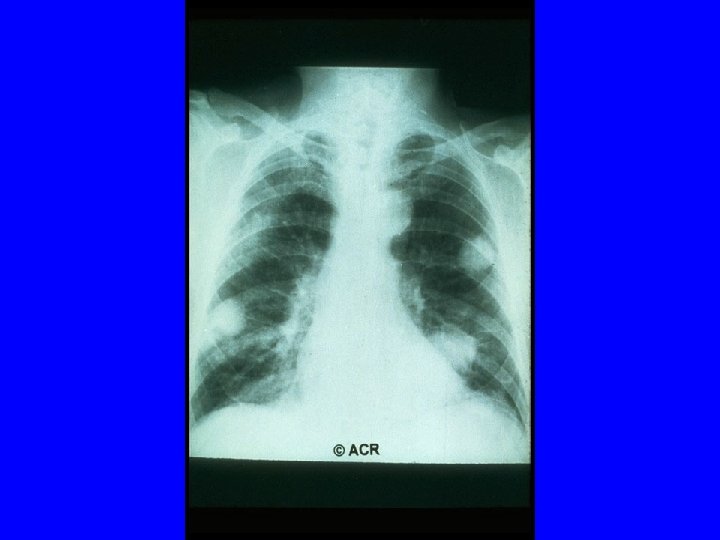

ACR 1987 Classification Criteria For Rheumatoid Arthritis Patients Must have Four of Seven Criteria Morning Stiffness Lasting at Least 1 Hour* Swelling in 3 or More Joints* Swelling in Hand Joints* Symmetric Joint Swelling* Erosions or Decalcification on X-Ray of Hand Rheumatoid Nodules Abnormal Serum Rheumatoid Factor * Must Be Present at Least 6 Weeks